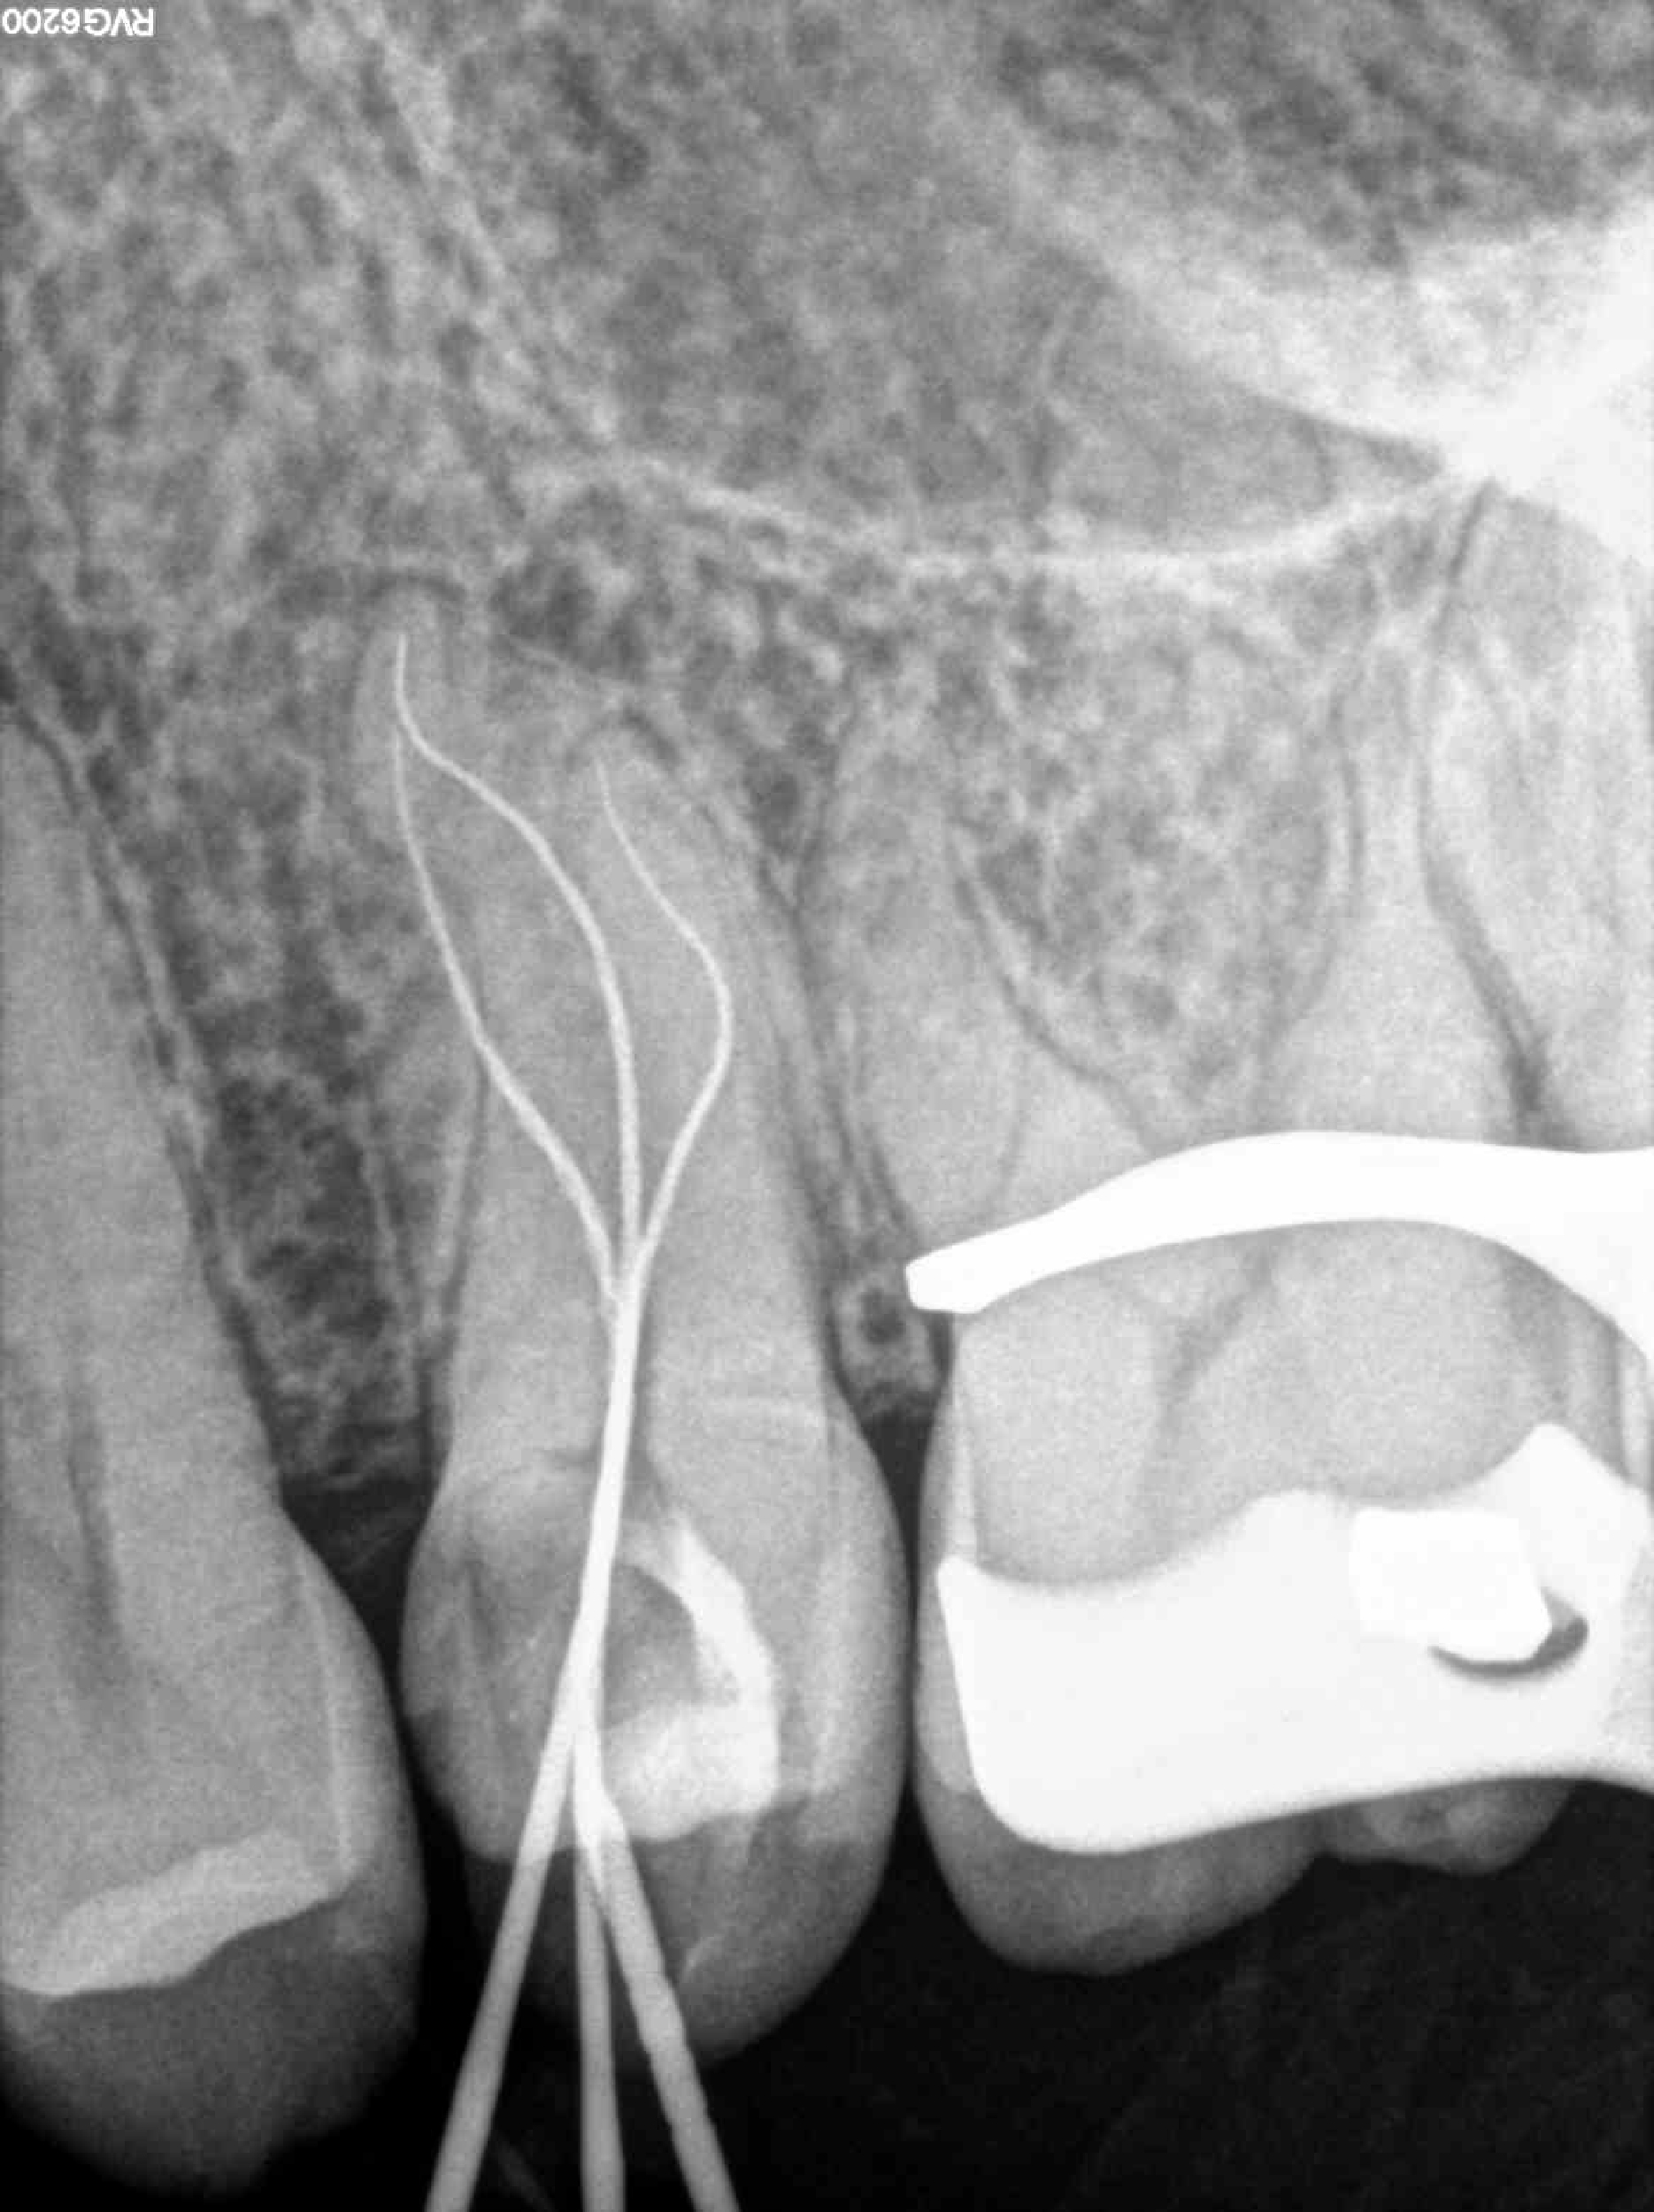

* Haz click sobre las radiografías para verlas a mayor tamaño

Haz click sobre las radiografías para verlas a mayor tamaño